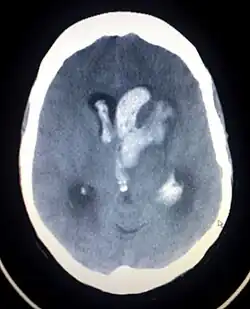

Casos de hipertensão pulmonar fatal e danos na válvula cardíaca associada a produtos farmacêuticos dos anorexígenos levaram à retirada de produtos do mercado na Europa. Este foi o caso do aminorex na década de 1960, e da fenfluramina em 1990.[4] Da mesma forma, a associação do inibidor de apetite fenilpropanolamina relacionadas com acidente vascular cerebral hemorrágico levou a sua retirada do mercado nos Estados Unidos em 2000, e preocupações semelhantes quanto a efedrina resultaram em uma proibição do órgão de controle de drogas americano (FDA) a sua inclusão em suplementos dietéticos, em 2004 (mais tarde um juiz federal anulou esta proibição, em 2005, durante um processo feito pela fabricante de suplementos nutracêuticos). Outro fator importante para a proibição da efedrina foi o seu uso como um precursor na produção de metanfetaminas.[5]